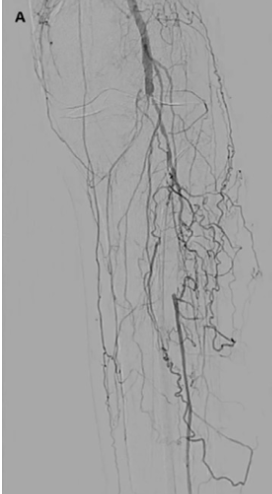

Optimal intravascular lithotripsy technique for Infrapopliteal intervention. Angioplasty remains the cornerstone of infrapopliteal intervention. Due to the lack of dedicated implants or approved bail-out therapies for infrapopliteal vessels, it is crucial to optimize the results of angioplasty while minimizing the likelihood of severe dissection or other vessel-related complications. We recently proposed an algorithm for optimal angioplasty of infrapopliteal vessels based on the concepts of optimal vessel sizing, selection of plaque modification technologies, prolonged balloon inflation, and careful assessment of postangioplasty dissection.80 Similar concepts apply to optimal application of IVL for infrapopliteal vessels (Figure 1).

When utilizing IVL for infrapopliteal angioplasty, we recommend inflating the IVL balloon to 4 atm and delivering at least 40 pulses per segment treated. In cases of longer lesions, multiple IVL inflations may be necessary. In these cases, we recommend approximately 10 mm balloon overlap to minimize geographic miss and ensure optimal angioplasty throughout the target lesion. Based on the 40 mm length of the S4 catheters, it is therefore possible to treat lesion lengths of 130 mm with a single balloon. For longer lesions, an additional IVL balloon can be used, or a technique of long angioplasty balloon inflation followed by “spot” IVL at areas of residual stenosis can be employed. With this technique, the likelihood of severe dissection or recoil is minimized. If there is continued stenosis or dissection after IVL, postdilation can be performed with an additional balloon, and scaffolds can be considered for cases of continued dissection. Figure 3, Figure 4, and Figure 5 demonstrate additional cases of IVL application for infrapopliteal lesions, with an emphasis on the sizing and techniques used for each case.